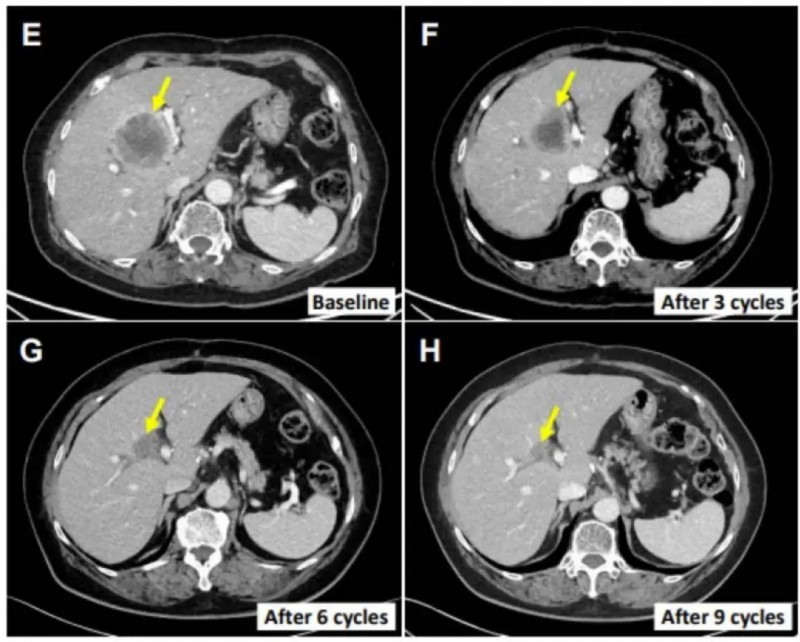

更令人动容的是一位76岁肝外胆管癌女性患者(E0217)的治疗奇迹!她既往接受过胆总管节段切除术与胆囊切除术,术后仅4个月便出现多处肝转移;后续接受吉西他滨联合顺铂全身化疗后疗效不佳,肝脏病变持续进展,抗癌之路陷入绝境。而在入组SMT-NK联合帕博利珠单抗治疗后,她的肝转移病变大幅缩小70.4%(详见下图E-H),且在初始治疗后12个月仍保持无进展状态——这份跨越绝境的持久疗效,为无数晚期胆道癌患者点亮了生命续航的希望!

▲图源“Cancers (Basel)”,版权归原作者所有,如无意中侵犯了知识产权,请联系我们删除